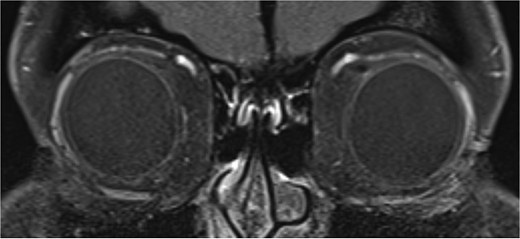

One month from initial presentation, the patient’s motility deficit progressed to bilateral moderate (−2) elevation deficit in adduction. A repeat MRI orbits yielded normal findings: there was no hypertrophy of the SO, no inflammation/hypertrophy of extraocular muscles, and no trochlear attachment (Fig. 3). Rheumatology input was sought regarding the possibility of acquired Brown syndrome; however, serology for mixed connective tissue disease, SLE, and rheumatoid arthritis was negative. The patient was treated for a total of 11 months on oral prednisolone at a maximum of 50 mg daily, which was slowly tapered and replaced with steroid-sparing, immune-modulating agents methotrexate and hydroxychloroquine.

T1 axial image of orbits which shows a normal trochlear-tendon complex.